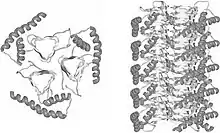

The infectious agent is a misfolded form of a host-encoded protein called prion (PrP). Prion proteins are encoded by the Prion Protein Gene (PRNP).[21] The two forms of prion are designated as PrPc, which is a normally folded protein, and PrPsc, a misfolded form which gives rise to the disease. The two forms do not differ in their amino acid sequence; however, the pathogenic PrPsc isoform differs from the normal PrPc form in its secondary and tertiary structure. The PrPsc isoform is more enriched in beta sheets, while the normal PrPc form is enriched in alpha helices.[19] The differences in conformation allow PrPsc to aggregate and be extremely resistant to protein degradation by enzymes or by other chemical and physical means. The normal form, on the other hand, is susceptible to complete proteolysis and soluble in non-denaturing detergents.[14]